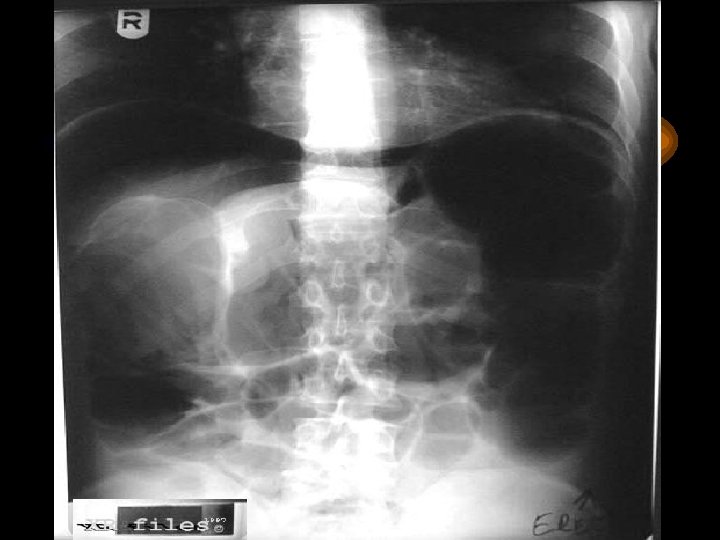

Kalın Barsaklar Perforasyon Divertikülit, kolitis, ani, şiddetli abdominal ağrı, rijidite Fekal peritonit, Ateş, lökositoz , şok Serbest hava (X-ray)